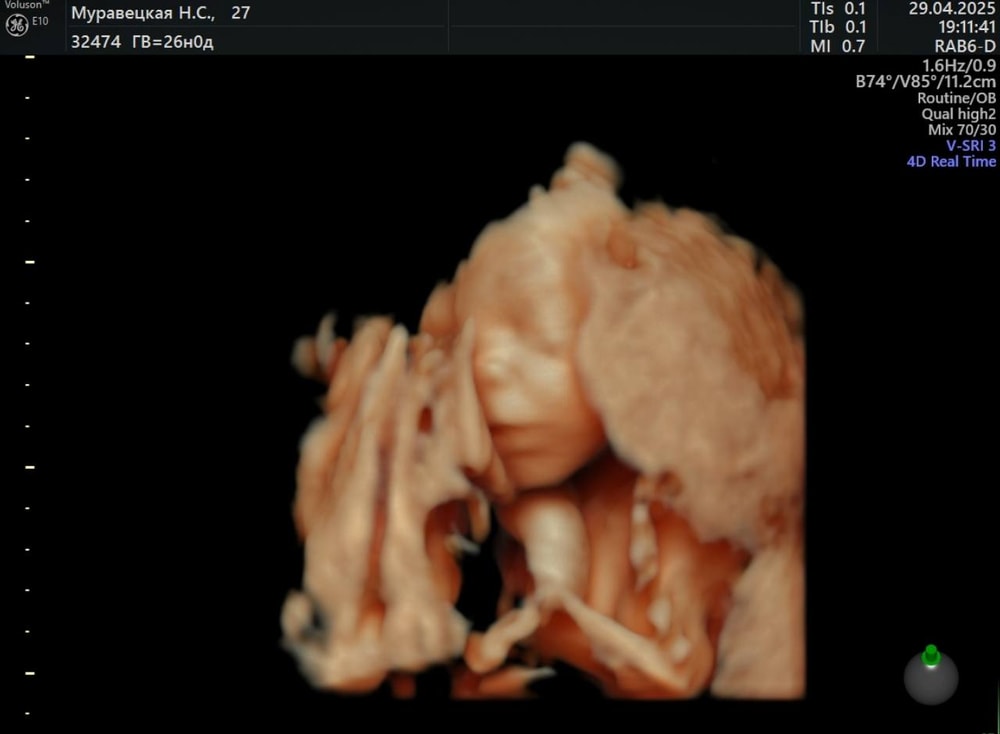

УЗИ

Была вчера у Сергея Александровича Тё. По УЗИ малыш опережает аж на 5 дней свой срок, весит 999 гр и длиной 34 см. На узи лежал не очень удобно, поэтому мы почти час делали исследование, крутились, вертелись, в итоге поймали личико 😊😍В прошлую пятницу прошла "всеми любимый" глюкозотолерантный тест. Мне так было жалко платить за него деньги (в ЖК дали направление аж в 30 недель почти, нас не будет в Москве), поэтому я пошла по ДМС к эндокринологу, чтобы мне дали направление на ГТТ, меня решили обследовать по-полной, поэтому я сдала еще биохимию с полным исследованием по железу, ОАК, ОАМ, ТТГ,Т4, гликированный гемоглобин. Все анализы в норме и даже ферритин 32!!!, я была в шоке, девочки, тк я пью пока по 1 таб сорбифера всего лишь, мне казалось к 3 триместру он рухнет до 0.